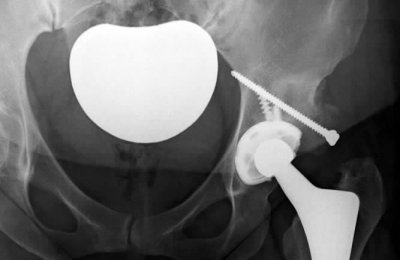

Below you will find a selection of common hip surgery procedures and rehabilitation techniques: